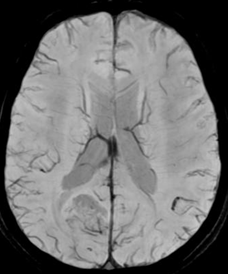

MRI study at admission revealed an ill-defined, irregular, heterogenous, nonenhancing, predominantly cortical-based bubbly appearing cystic lesion involving the right posterior parietal lobe with no perilesional edema – findings that were compatible with a diagnosis of DNET – Type 2 (Figure 1-7).1

Figure 2 Axial fluid-attenuated inversion recovery (FLAIR) MR images. Lesion appears hypointense with respect to normal white matter and isointense to intraventricular CSF, with some hyperintense internal septa. A well-defined hyperintense rim separating the tumor from the surrounding normal brain is visible (arrow). This is referred to as the FLAIR hyperintense ring sign.